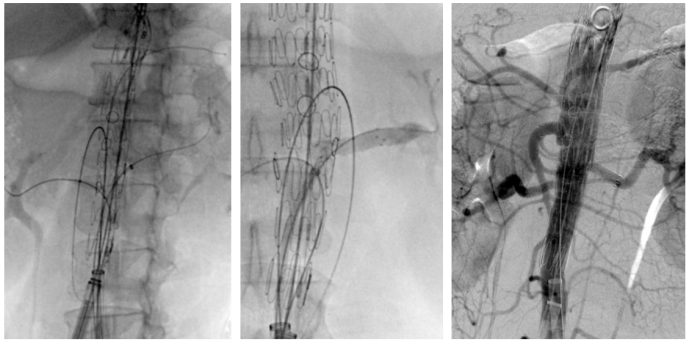

★ 鞘管与导管的“黄金搭档”

Fustar、FusmartTM等可调弯器械的出现使完全经下肢动脉入路修复成为现实。

双大鞘,支架全放开,保持束径,保留后释放。

Fusmart流程:调弯选进;调直跟踪泥鳅导丝至动脉远端;交换硬导丝;退出Fusmart。

Fustar流程:调弯辅助Fusmart选入分支动脉;调直并回退Fustar;导入鞘芯(保持调直状态),循硬导丝到分支动脉,鞘需要超过窗口;